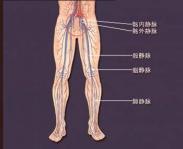

下肢交通静脉瓣膜关闭不全

628健康网为您分享有关下肢交通静脉瓣膜关闭不全的症状,下肢交通静脉瓣膜关闭不全的治疗方法,下肢交通静脉瓣膜关闭不全...

血栓性静脉炎

628健康网为您分享有关血栓性静脉炎的症状,血栓性静脉炎的治疗方法,血栓性静脉炎的预防知识,血栓性静脉炎的症状图片,血...

上肢深静脉血栓形成

628健康网为您分享有关上肢深静脉血栓形成的症状,上肢深静脉血栓形成的治疗方法,上肢深静脉血栓形成的预防知识,上肢深静...